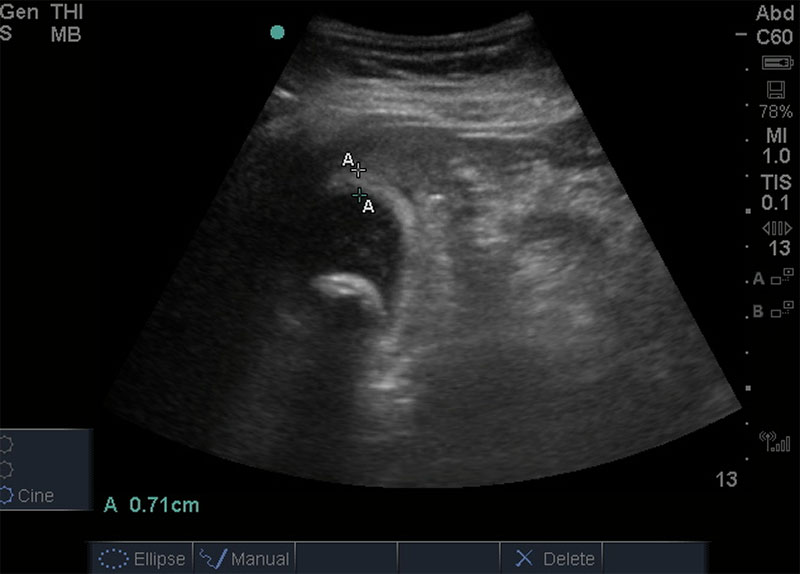

40 y/o female with history of hyperlipidemia, obesity, and GERD presenting with upper abdominal pain. The goals of this case are to evaluate initial evaluation of young female with upper abdominal pain and review ultrasound findings of acute.